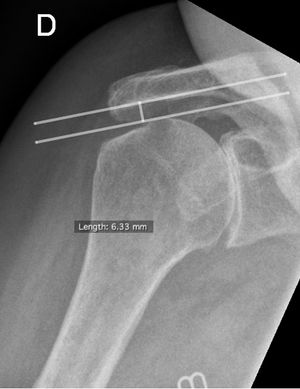

Acromiohumeral Distance

Tendinopathies of the rotator cuff are frequent pathologies which may have as their origin intrinsic and/or extrinsic factors. A magnetic resonance imaging or computed tomography allows these lesions to be visualized with good precision. However, a standard X-ray marker was described long ago. This is the subacromial space (Figure). In the 1960s, Golding was one of the first to describe a link between the decrease in subacromial space and rotator cuff disease.[62] Later in 1970, Weiner et al. also describe an association between the reduction of the subacromial space and the tear of the rotator cuff.[63] In 1984, Petersson describes the average distance of 9 to 10 mm for a normal acromio-humeral space, with a pathological threshold suspecting a lesion of the supraspinatus at 6 mm.[64] Thus, in the years that followed, many authors came to the same conclusion with a widely described association between a subacromial space less than 7 mm and a massive rupture of the rotator cuff[65][66][67][68][69] with a massive rupture of the rotator cuff described as a tear of at least two tendons, often the supraspinatus and infraspinatus.[70] Thus, Saupe et al. show in the study a strong association of the decrease of the subacromial space to less than 7 mm and a tear of the supraspinatus and infraspinatus.[65] Nové-Josserand et al. explain that a decrease of the subacromial space to less than 7 mm indicates a rupture of the infraspinatus. The reduction of the space is due to the loss of the infraspinatus lowering function with a migration of the humeral head in the space deserted by the supraspinatus. Furthermore, there is a higher rate of recurrence of rupture after surgery in a patient with a massive rupture of the cap and therefore a decreased subacromial space. Moreover, the radiological measurement showed a very good correlation whether it is compared to the scanner[71] or when comparing inter-observers.[72][73][74] All these elements therefore make it possible to use the measurement of the subacromial space in the evaluation and the therapeutic decision-making of a patient with shoulder pain. However, this remains a good indicator in the evaluation of the posterior superior cuff without giving information on the anterior cuff.[75] In connection with the reduction of subacromial space, Hamada et al. introduced in 1990 the notion of arthropathy linked to a massive rupture of the rotator cuff.[7] It declines in 5 grades progressive, each associated with radiological changes. In 2005, Walch et al. modified this classification somewhat by creating two subtypes of grade 4. However, the same year, Nové-Josserand et al. show that there is no linear progression of the Hamada classification.[76] However, it confirms that the tendinopathy of the rotator cuff is more involved in the aging of the shoulder than the osteoarthritis. A new study proposed in 2011 by Hamada et al. examines in more detail the different implications in terms of grades.[77] The greater role of a lesion involving the subscapularis from Grade 3 and a rate of recurrence of rupture after intervention more frequent from Grade 2. Thus, surgery should be considered before the subacromial space is reduced.